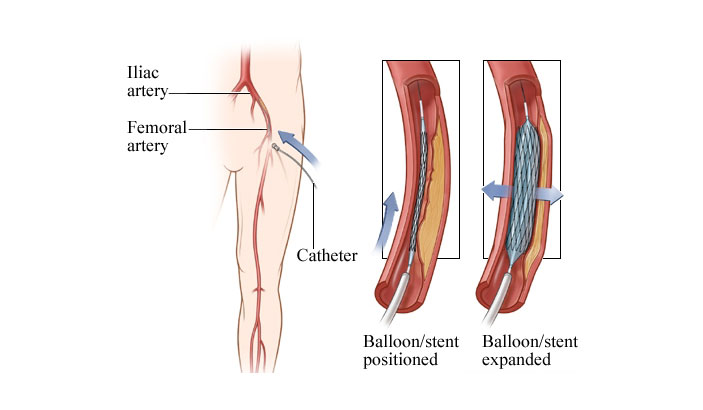

Value added benefits of the Coronary Angioplasty:

Value added benefits of the Angioplasty PTCA :

Value added benefits of the Renal Angioplasty:

Value added benefits of the Vertebral Angioplasty: